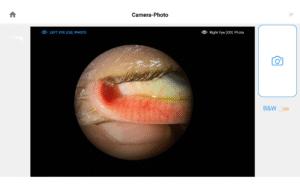

Pushing ahead, our imaging system includes our new, patent-pending Halo background light. Working with native slit lamp illumination, Halo delivers unparalleled clarity of the ocular adnexa. You’ll uncover details of the meibomian glands, acinar spaces, conjunctiva, lid margins, and lashes like never before.